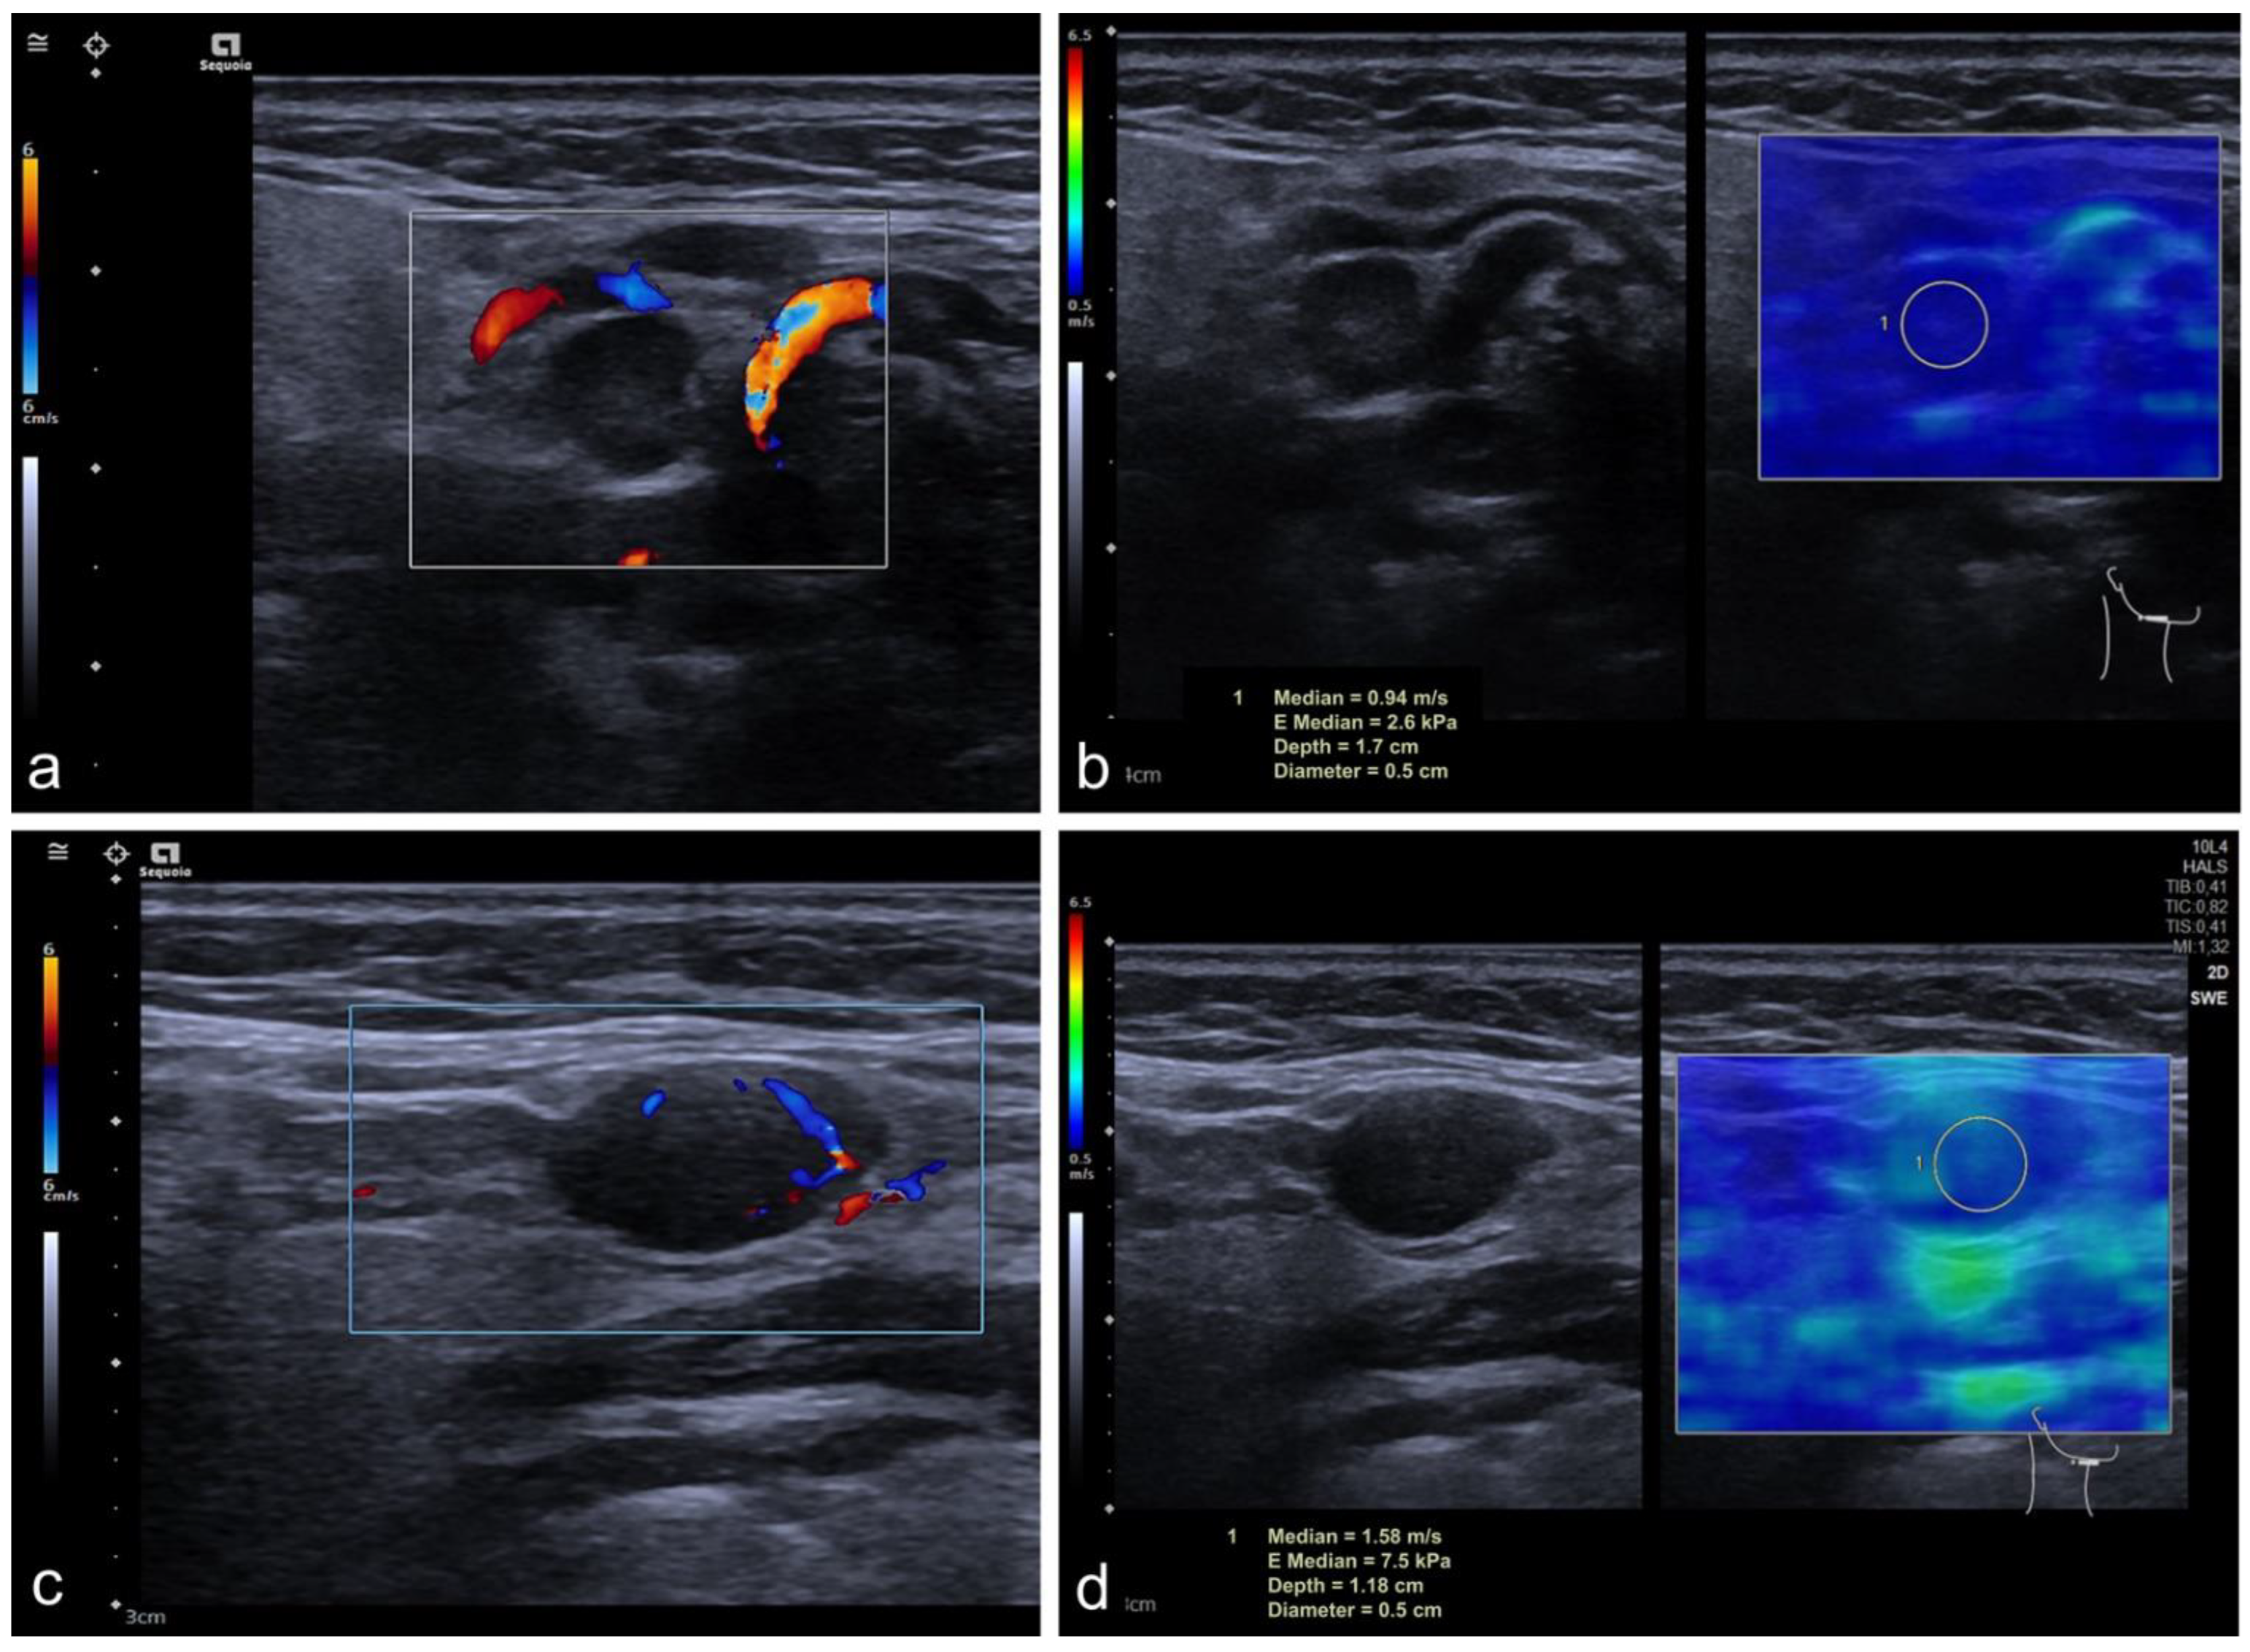

2.2. Imaging Protocol

3.3. Subgroup Solbiati Index > 2

3.4. Infracentimetric CLN